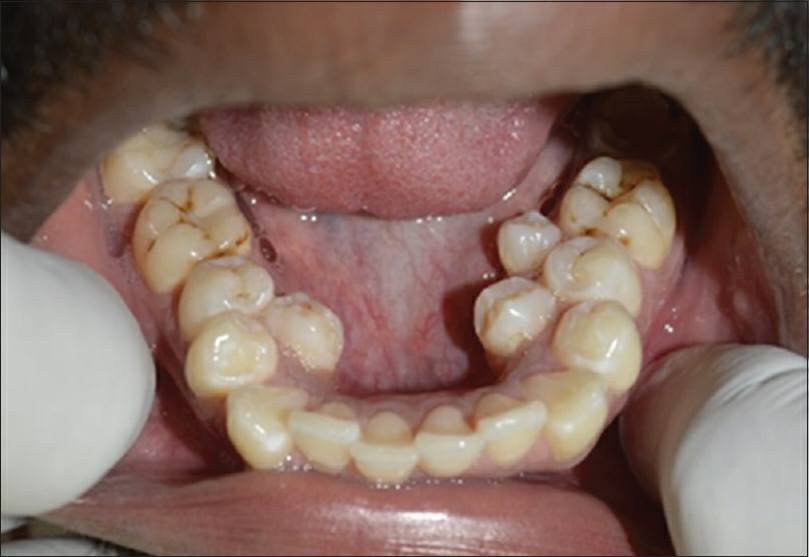

Susunan Gigi Tidak Teratur Menyukarkan Klinik Pergigian Desa Murni Facebook